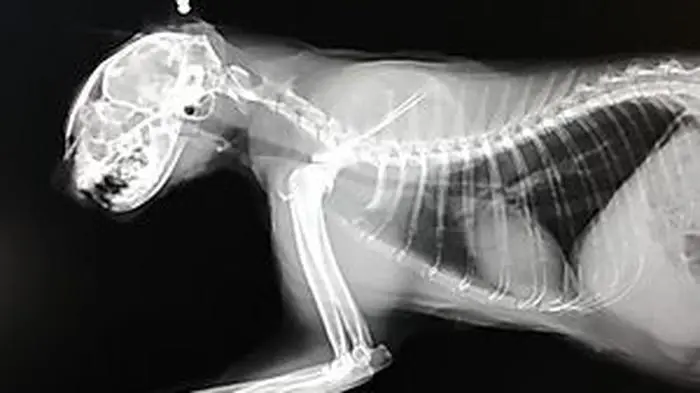

Das Röntgenbild der dritten Katze mit dem Projektil, das entfernt werden konnte